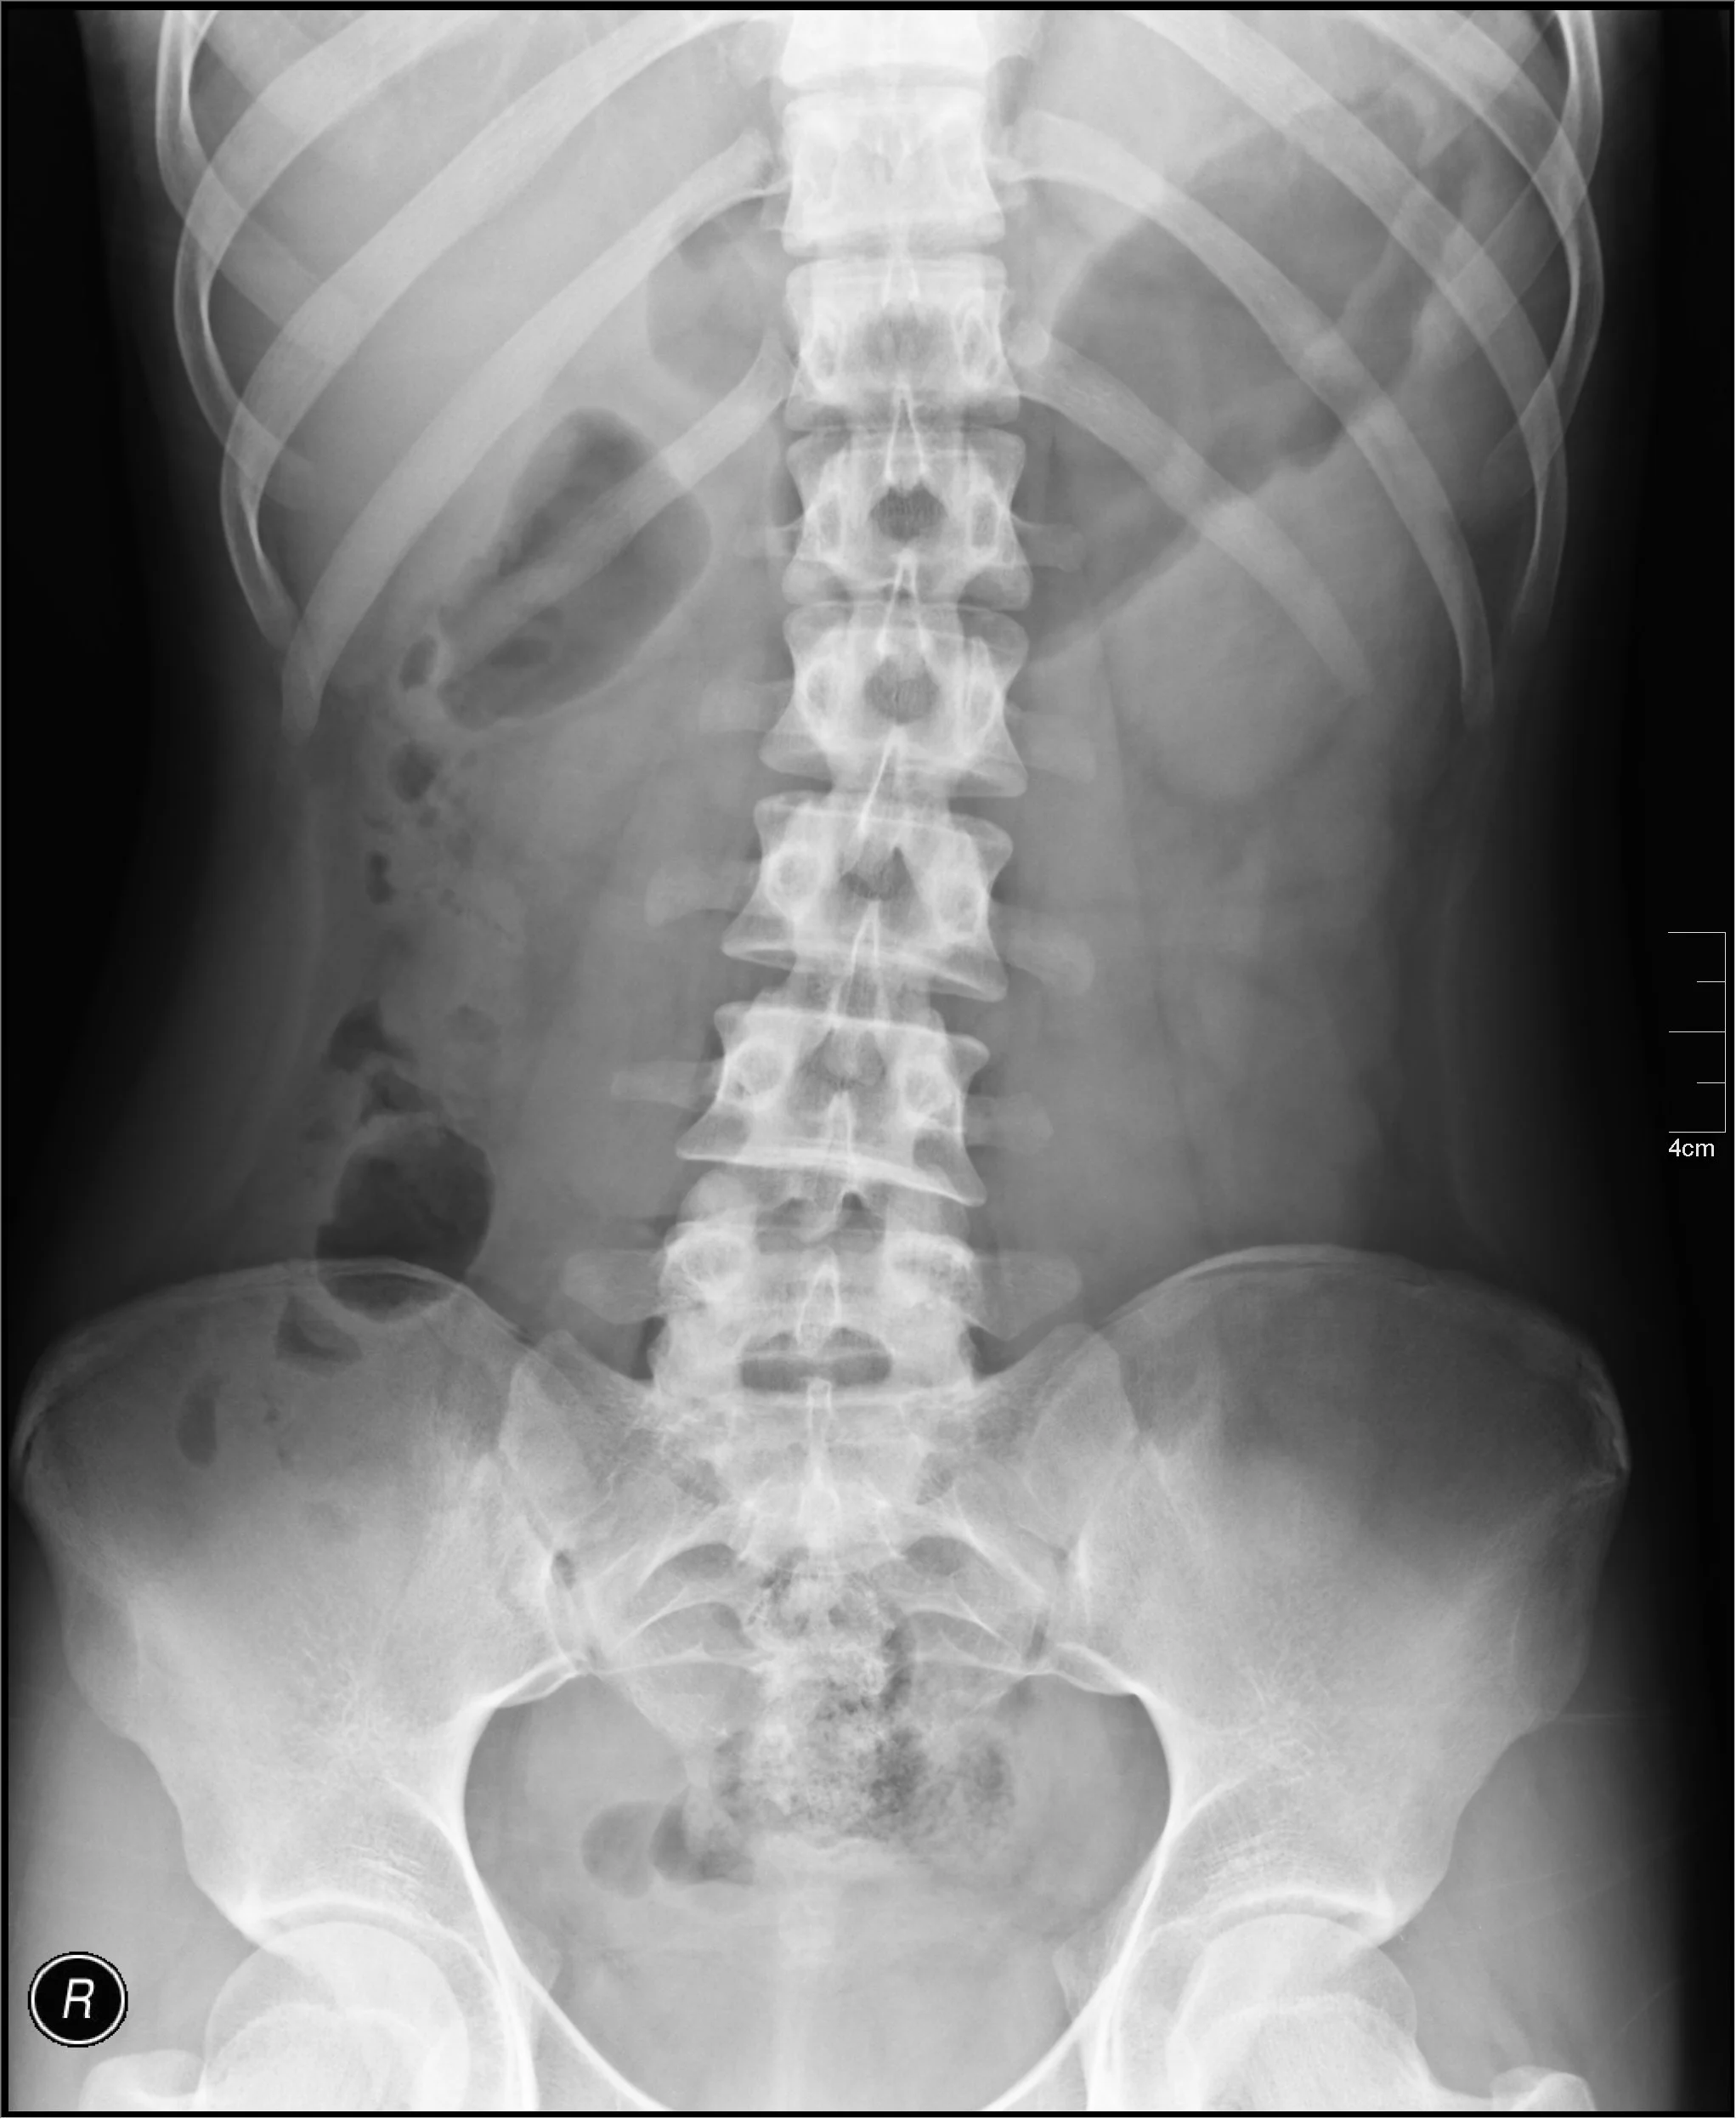

Visualize internal structure to see if pre-existing disease processes are present, such as:

- Spinal disc disease

- Spinal Stenosis

- Vertebra Fusions

- Unlevel Pelvis

- Lung Disease

- Abdominal aortic aneurysm